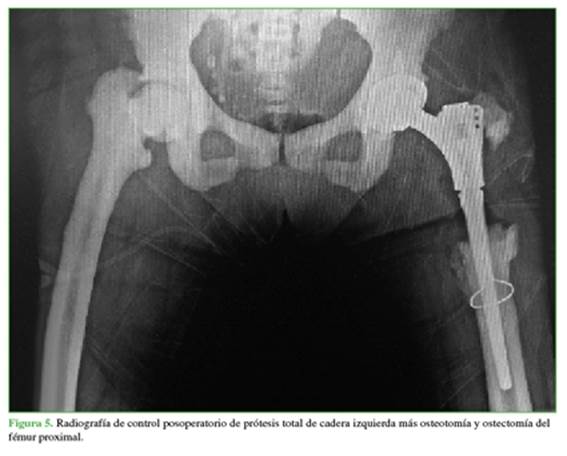

En febrero de 2018 se realiza dicha intervención más osteotomía correctora de fémur proximal y ostectomía proximal a nivel del trocánter por abordaje posterolateral, sin complicaciones. Se implanta acetábulo no cementado 44 x 28, 4 tornillos de fijación acetabular, inserto de polietileno altamente entrecruzado 44 x 28, vástago de revisión no cementado 140 mm x 13 mm con metáfisis proximal, con aleta para fijación de mecanismo abductor de la cadera y cabeza de cromocobalto 28M (Figura 5).